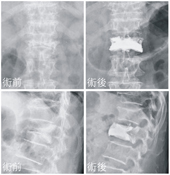

「經皮椎體成型術」藉由長針將骨水泥注入因壓迫性骨折而塌陷的椎體,可以有效緩解疼痛,甚至矯正駝背變型。